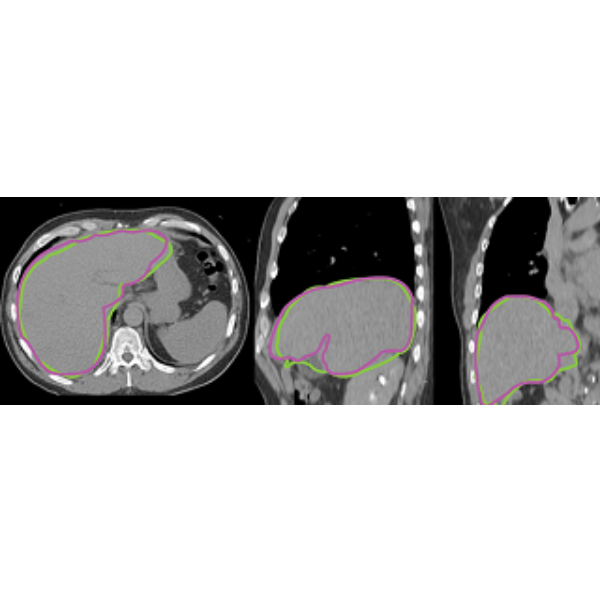

- Timesaving tools for liver, lungs, and tumor VOI generation.

- Divide liver into lobes or segments based on your post-treatment goals.

Multiple modality image fusion is available, allowing comparison of PET, SPECT, CT, MR, and CBCT. Deformable image registration is also included for cases where there are differences in positioning, size, and organ movement.